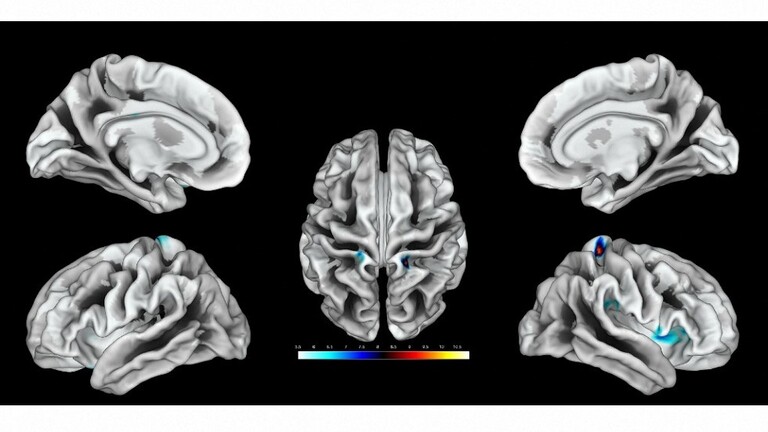

وبحثت الدراسة مرحلة إزالة أو نزع الاستقطاب في القشرة الدماغية البشرية وقدمت فهما أفضل لكيفية استجابة الدماغ لنفاد الطاقة، حيث قدمت لأول مرة فهما كاملا حول الفيزيولوجيا الكهربية للموت الذي يحدث عقب توقف الدورة الدموية في الدماغ البشري.

وأشار المقال إلى وجود دراستين جديدتين ستنشران في مجلة "Brain" العلمية، قام بهما فريق من العلماء كجزء من دراسة كبيرة تركز على مرحلة إزالة الاستقطاب في الدماغ، حيث وصف العلماء لأول مرة مرحلة "الموجة الكهربائية" للموت الدماغي.

وقال درير إن انتشار عمليات إزالة الاستقطاب أو "تسونامي الدماغ"، تعتبر بجميع المقاييس من أكبر الأحداث التي تصيب الدماغ الحي، وهي أشد من نوبات الصرع وتتعلق بالتغيرات الأيونية وتغيرات الناقل العصبي والتغيرات الكهربية والعديد من الجوانب الفيزيولوجية المرضية الأخرى التي تصيب الدماغ، وترتبط بتدفق كمية هائلة من الماء إلى الخلايا العصبية، مما يؤدي إلى تضخمها.

إلى ذلك، ذكرت الدراسة أن "هذه الموجة المنتشرة القابلة للعكس والتي يمكن عكسها تبدأ عادة بعد 2 إلى 5 دقائق من ظهور نقص التروية الحاد، مما يشير إلى بداية تغير عصبي سام يؤدي في النهاية إلى إصابة لا رجعة فيها".

وأجرى العلماء تسجيلات من خلال تركيب شرائط أو صفائف قطب كهربائي لدى المرضى الذين تعرضوا لتلف دماغي حاد أدى إلى دخولهم في حالة لا رجعة منها أو ميؤوس منها تستوجب فقط بعض العلاجات التخفيفية بدون وجود فرصة للإنعاش.